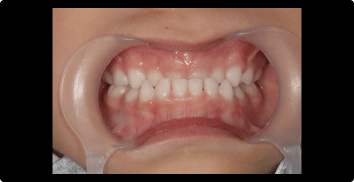

症例1:受け口の矯正治療

BEFORE

AFTER

症例概要

年代・性別

10歳代 女性

主訴

上下反対の噛み合わせが気になる

治療内容

ムーシールドを用いた矯正治療

治療期間

4ヶ月

治療のリスク

装置の装着時間を守らないと、治療結果が伴わない場合があります

治療費用

440,000円(税込)